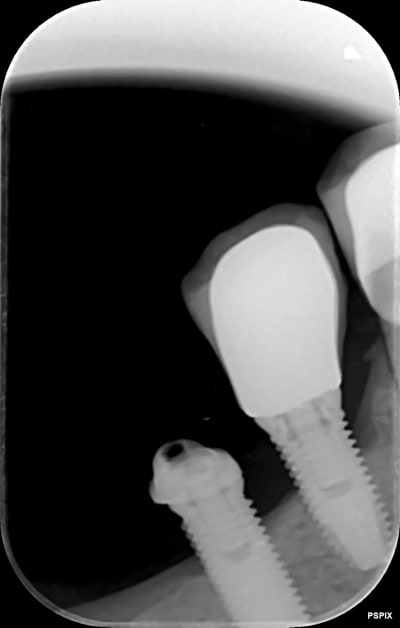

Identification implant

je ne suis pas sur a 100%, pour identifier ces implant.

Branemark??

Nobel mk3

https://whatimplantisthat.com/implants/details/branemark-mk-iii-np

et un speedy pour l'implant en 4 (ou 5....bref le plus antérieur)